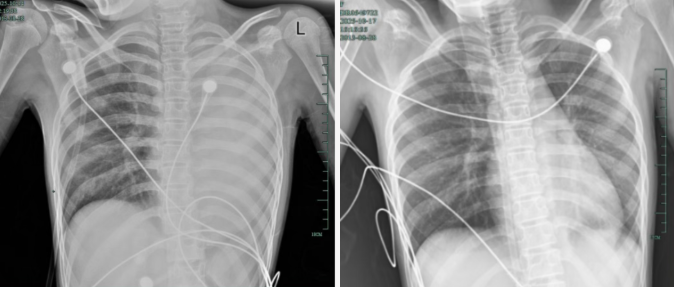

治疗前,左肺呈“白肺”状态;治疗后,“白肺”被吸收,心脏边缘清晰可见

入院后,她很快出现呼吸急促、胸闷胸痛,体温38.5℃,只能靠 5L/min 的面罩吸氧维持血氧,胸片显示左肺已完全呈 “白肺” 改变,肺部炎症进展迅猛。

后续检查发现,引发她此次感染的是毒力极强的铜绿假单胞菌,多发生在免疫功能低下人群。经过精准抗感染、祛痰、抗炎等系列治疗,孩子逐渐康复,已顺利出院。庆幸的是,笑笑的“白肺”基本吸收,恢复如常,没有留下严重的并发症。